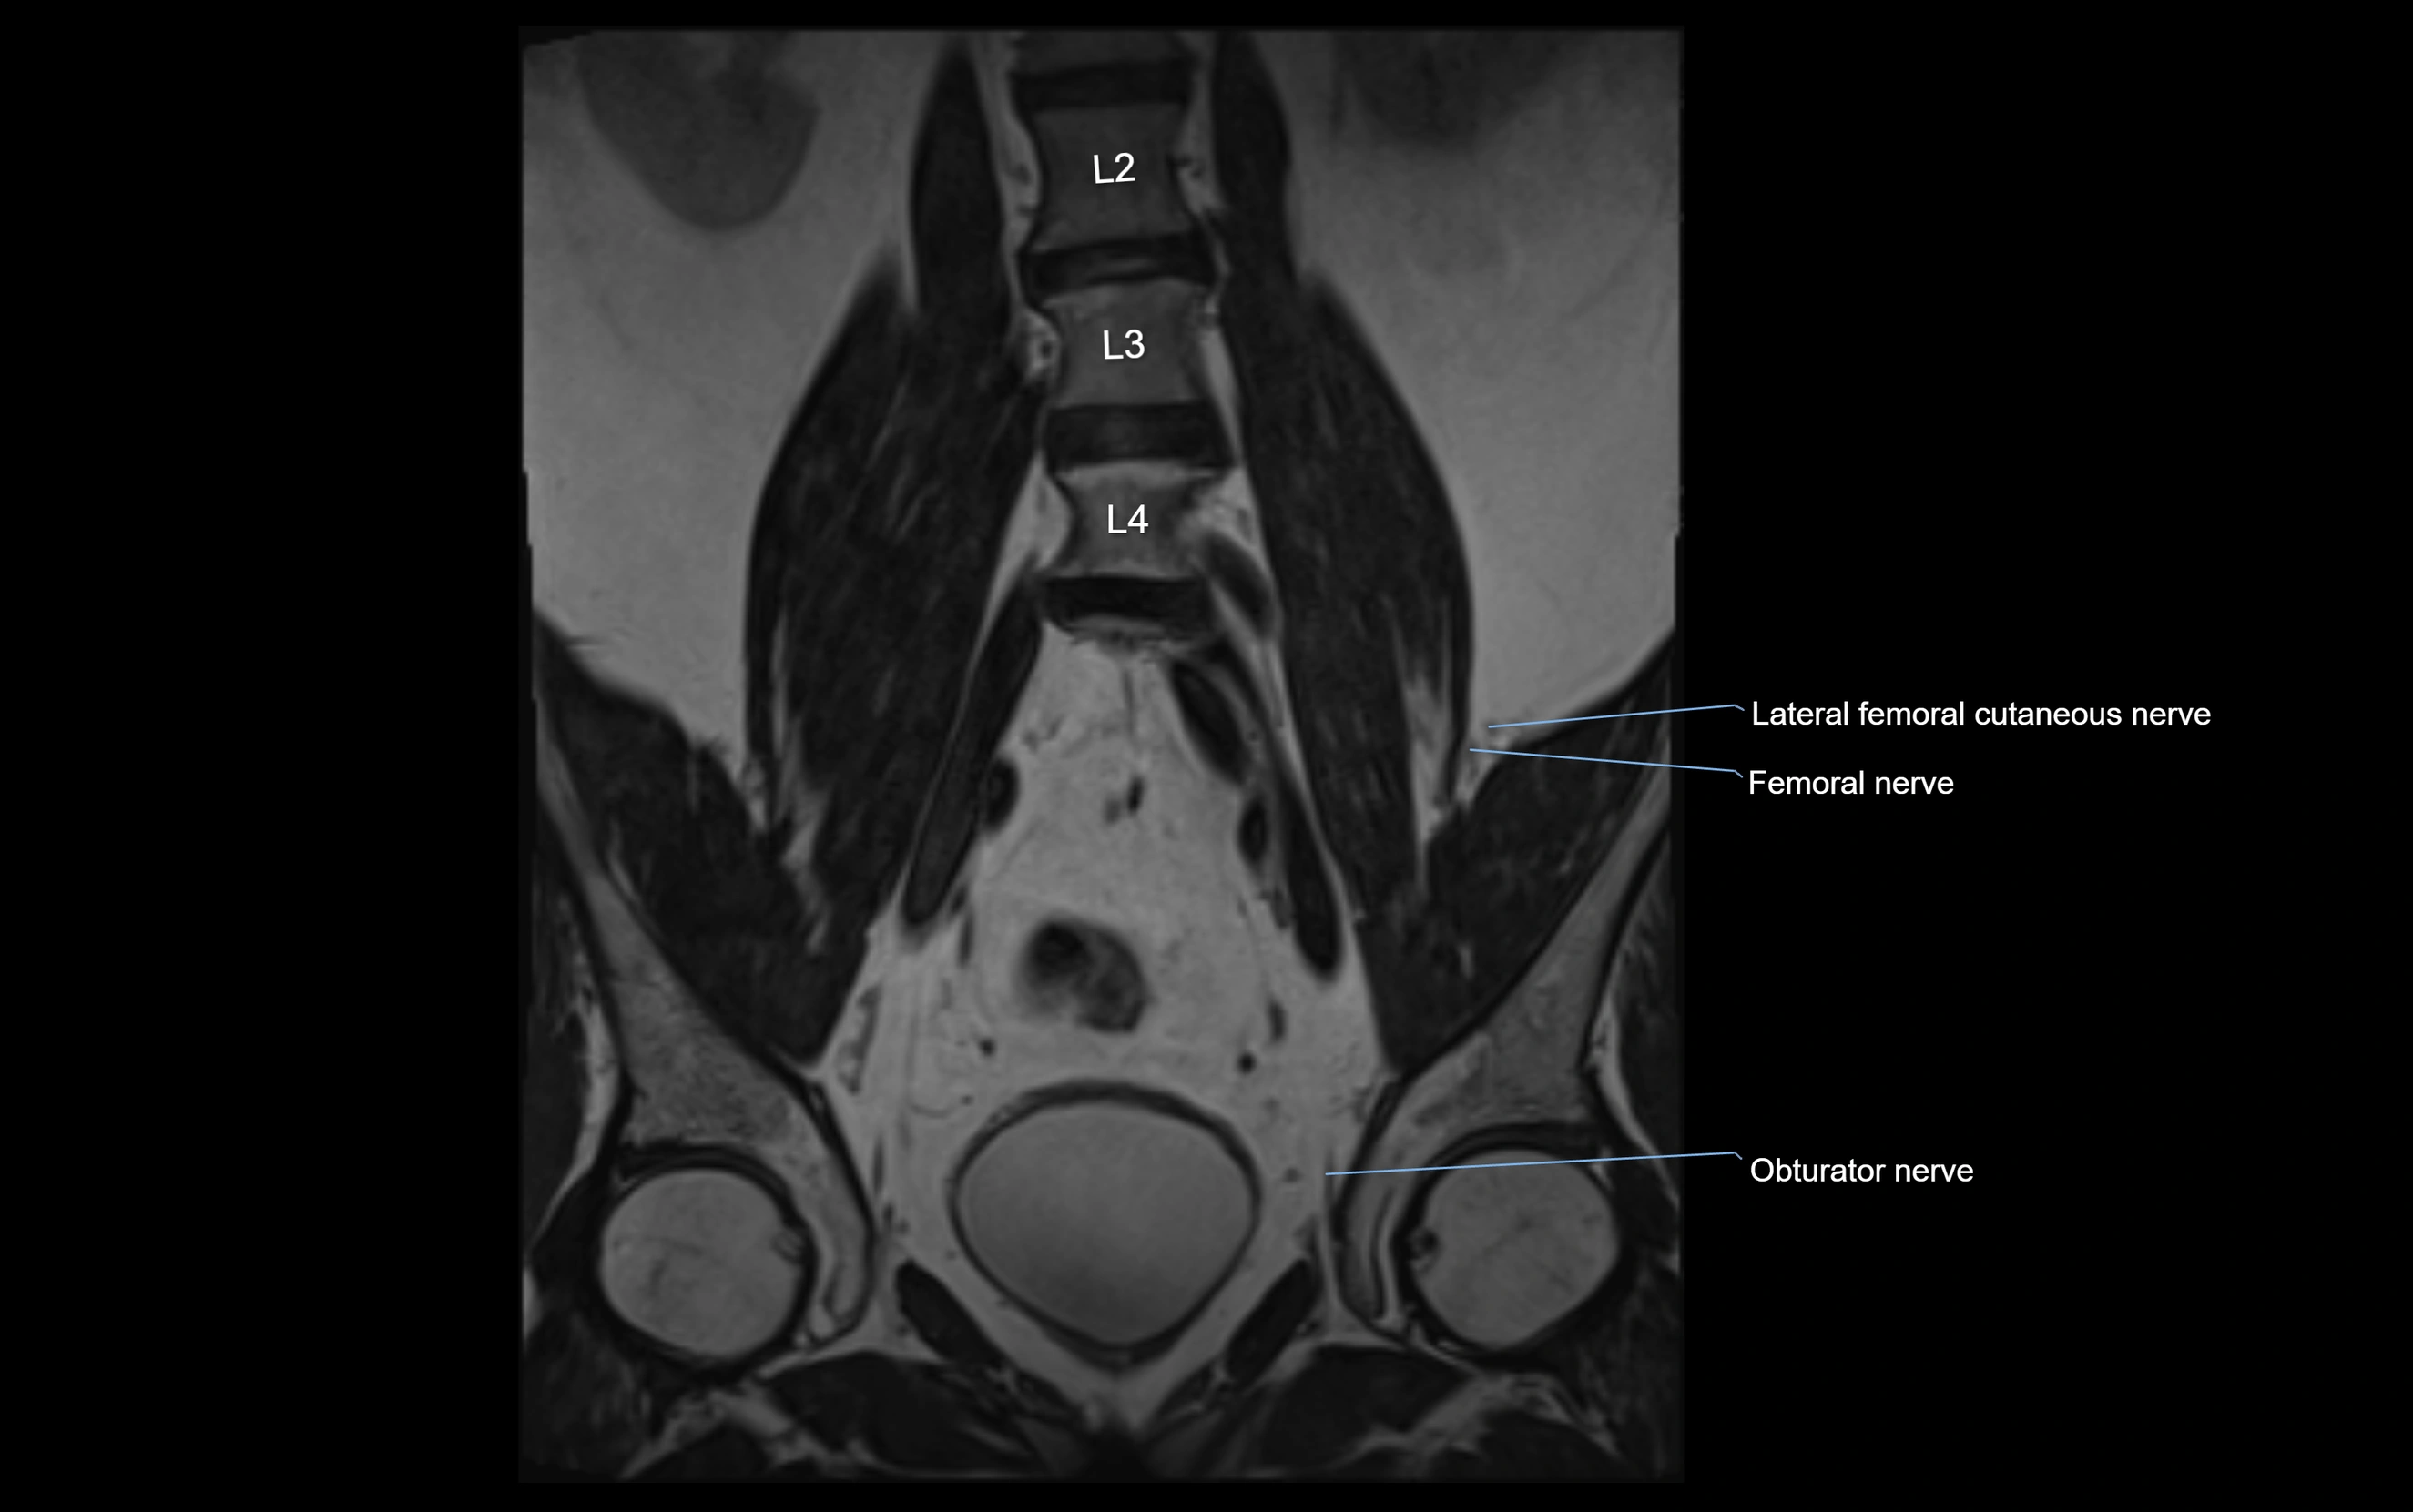

MRI Appearance

T1-weighted images:

• Nerve appears as a very thin low-to-intermediate signal intensity structure

• Surrounded by bright fat, aiding visualization

T2-weighted images:

• Nerve shows intermediate to mildly hyperintense signal compared to muscle

• Pathological involvement appears brighter

STIR (Short Tau Inversion Recovery):

• Normal nerve appears dark

• Inflamed or entrapped nerve appears bright hyperintense

T1 Fat-Sat Post-Contrast:

• Normal nerve enhances minimally

• Pathologic nerve (neuritis, entrapment, tumor infiltration) shows focal or diffuse enhancement

3D T2 SPACE / CISS:

• Nerve appears intermediate to mildly hyperintense compared to muscle

• Surrounded by bright fat or CSF, improving visualization

• Best sequence for mapping small pelvic nerves such as the anococcygeal

MRI image

image